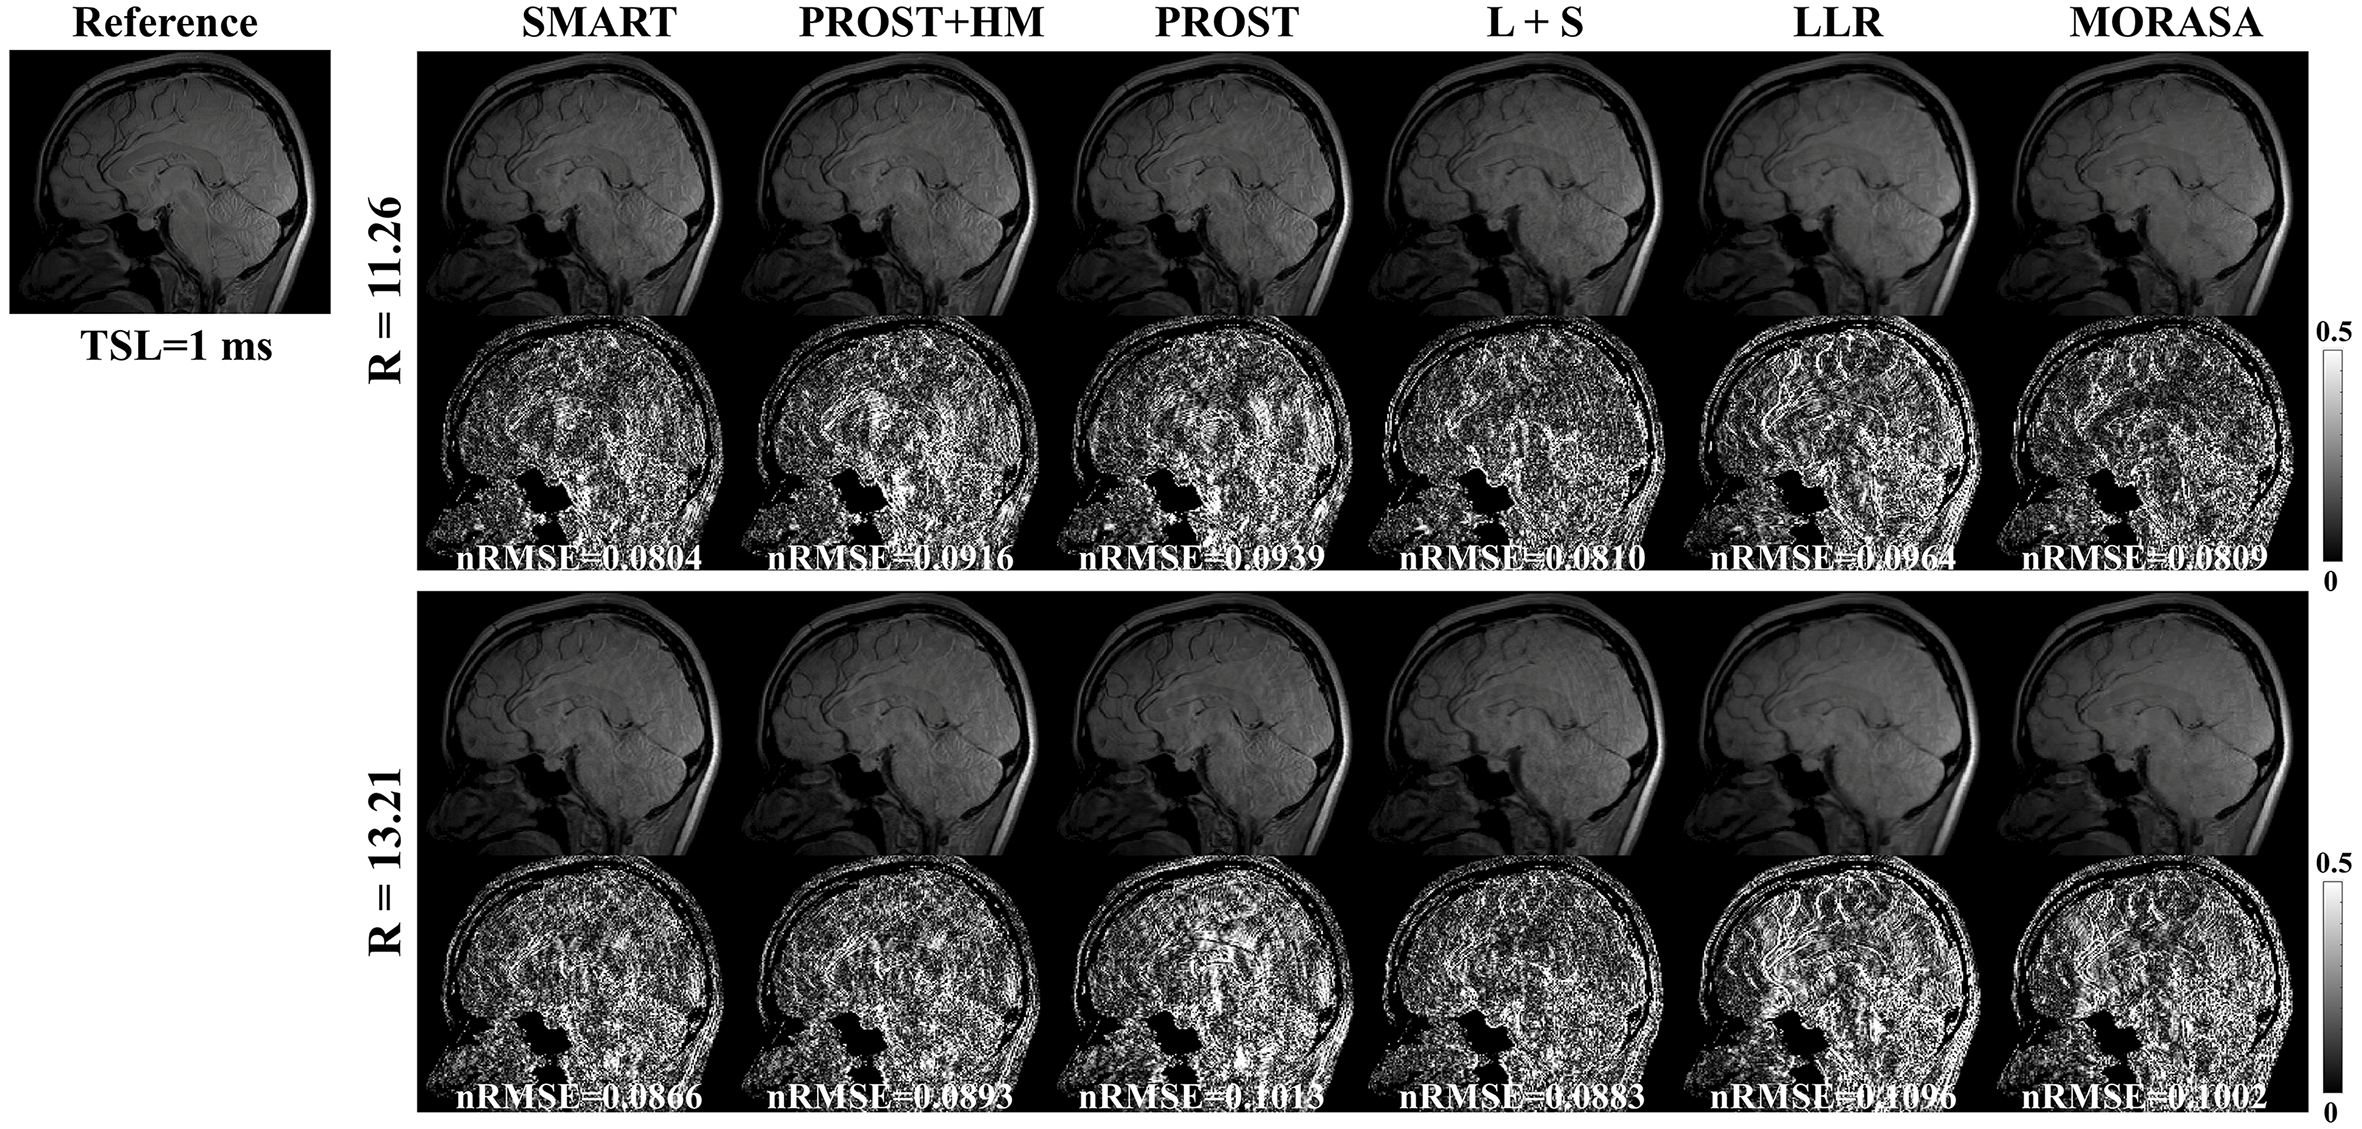

The -weighted images (at TSL = 1 ms) from one slice of the reconstructed 3D images using the SMART, PROST + HM PROST, L + S, LLR, and MORASA methods for R = 6.76 and 9.04 are shown in Fig.7. The maps reconstructed using the methods above are shown in supplementary information Fig. S5.

4.4.1 Low acceleration with 6.76-Fold and 9.04-Fold

4.4.2 Low acceleration with 11.26-Fold and 13.21-Fold

Fig. 8 shows the reconstructed -weighted images and the related error maps at TSL = 1 ms with R = 11.26 and 13.21 using the six methods in 3D imaging. The estimated maps from the reconstructions are shown in supplementary information Fig. S6. At high acceleration, the low-rank tensor-based reconstruction methods (SMART, PROST, and PROST+HM) show better detail retention than the low-rank matrix-based methods (LLR and MORASA). The SMART method still achieves lower nRMSE than other methods at higher accelerations.